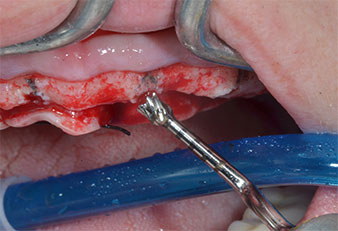

Пиезоелектрически инструмент с диамантено покритие с форма на пламък (Piezomed I1) e използван за маркиране на позициите на имплантите и за пилотна подготовка (Фиг. 3). Препарацията беше извършена с внимателни вертикални движения, с намалена мощност, пълна иригация и лек натиск (под 300 g) След това се приложи пилотен инструмент (Piezomed I2A/ I2P) за първоначално увеличение на диаметъра на имплантното ложе с 2 mm (Фиг. 4), последвано от 3 mm разширение (Фиг. 5)

Инструменти I2A/I2P за Piezomed

Фиг. 4 Следващата стъпка е пилотно разширяване с накрайници I2A/I2P, които прилагат ротационно хоризонтално движение.